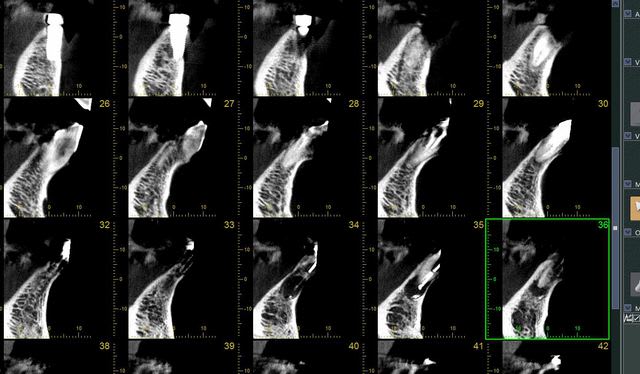

je ne me lasse pas de mon dernier joujoux...

quel précision!

implants posée le matin même..

comme on calibrait la morita, j'en ai profité pour faire un champs 10*8

je sens que je vais apprendre à poser des implants avec les contrôles post op.

en Russie le scanner est obligatoire tout les ans à la suite d'une pose d'implant. un peu excessif mais cela permet d'avoir du recule sur la façon dont pose ses implants.